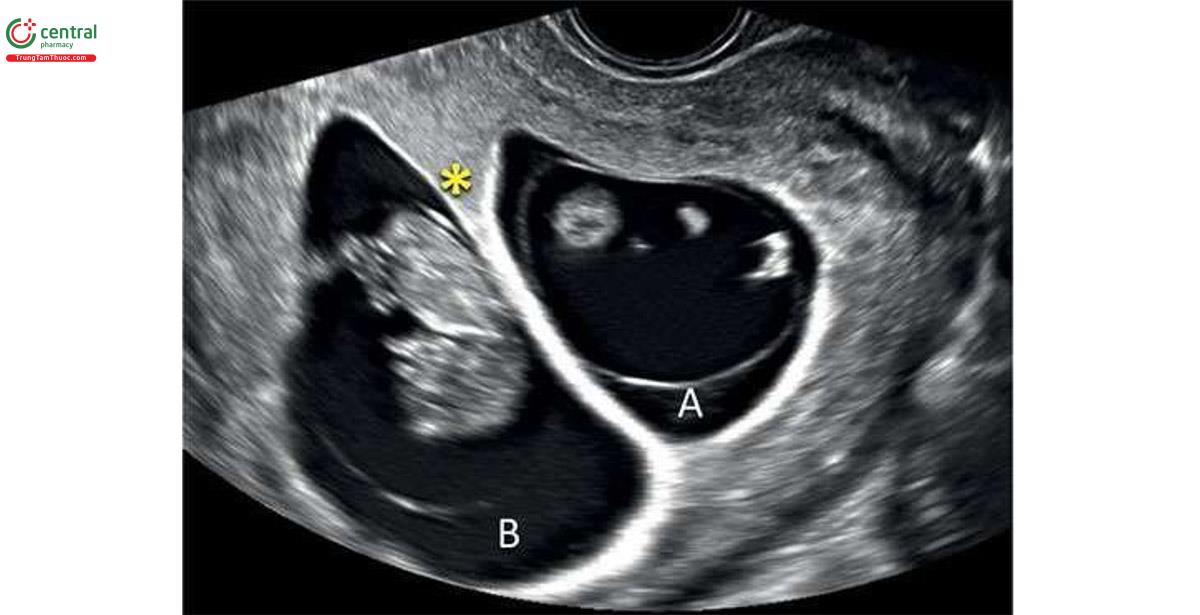

9 неделя близнецов

9 неделя близнецов 111 фотографий